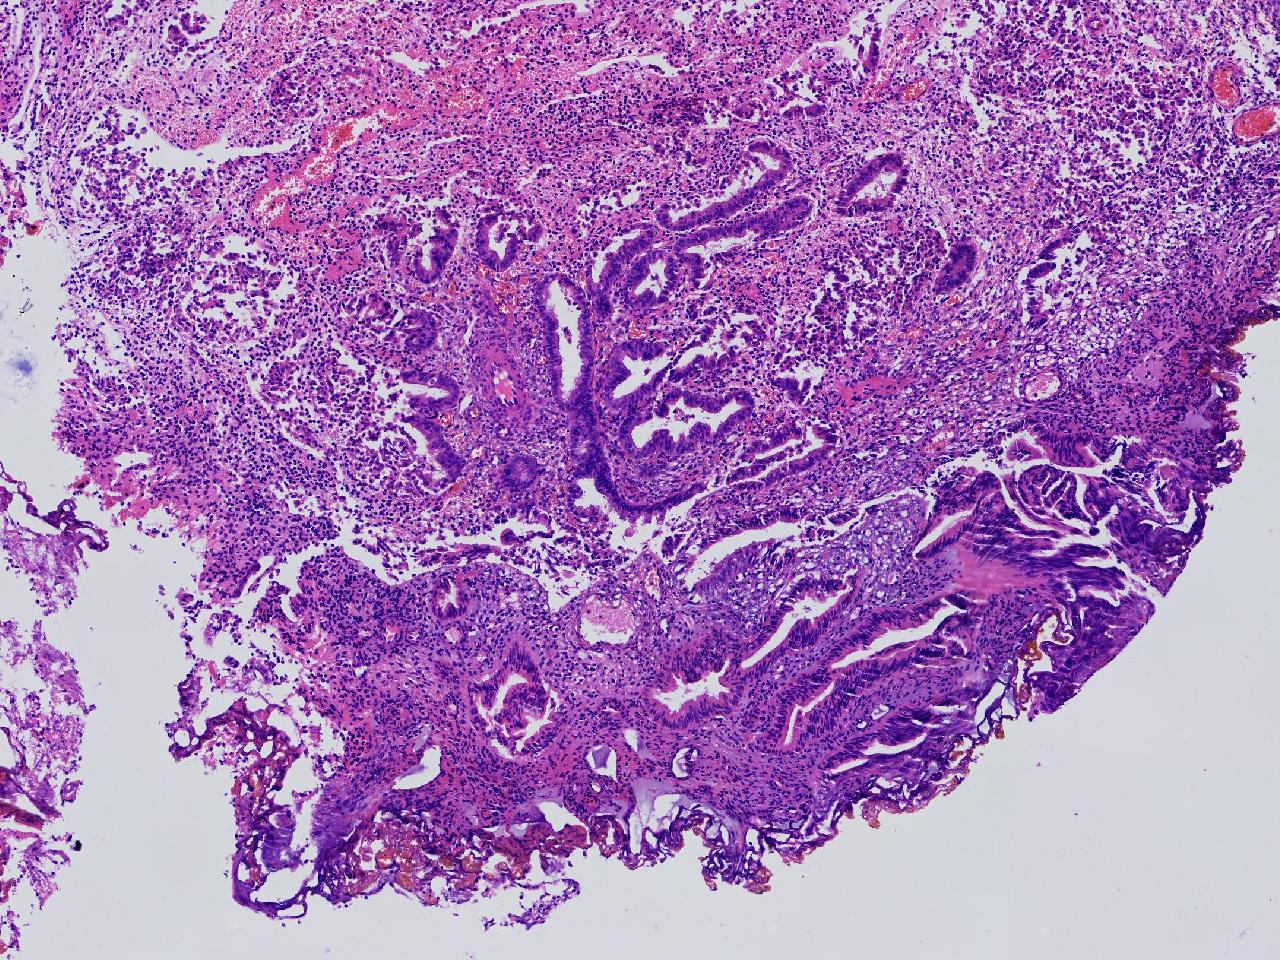

请教。1.有没有非典? 2.内膜是什么变化?

女,50岁,彩超示:粘膜厚度1.1cm。宫腔可见数个高回声,提示宫腔息肉。

子宫内膜+内膜息肉

灰粉色不整形软组织多块,3X3X2厘米。

子宫内膜息肉。

没有非典。

无非典型性子宫内膜增生,子宫内膜息肉

无非典内膜伴息肉。